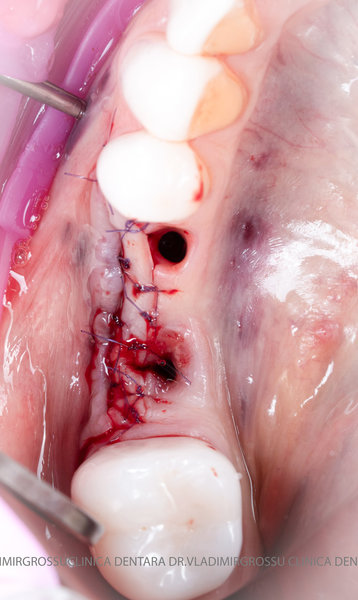

După extracția dentară, în intervalul de 6-12 luni, osul alveolar suferă un proces natural de remodelare, ceea ce conduce la scăderea volumului osos prin rezorbție. De aceea, inserția implantului dentar este ideală imediat după extracție sau, cel târziu, în primele 3-4 luni după aceasta.Scopul procedurilor de adiție osoasă este refacerea fundației osoase necesare pentru stabilizarea corectă a implantului dentar. Pentru ca un implant să reziste în timp la forțele masticatorii, este nevoie de o bază osoasă solidă și sănătoasă.

Procesul de refacere osoasă este complex, însă, simplificat, se bazează pe faptul că osul adăugat se integrează treptat, fiind înlocuit parțial cu os natural, oferind astfel suportul necesar implantului.

Un element esențial în procedura de aditie osoasă este utilizarea membranelor biologice, care izolează materialul osos de țesuturile moi (gingie) pe durata procesului de vindecare. Cele mai recomandate sunt membranele resorbabile din colagen sau pericard.